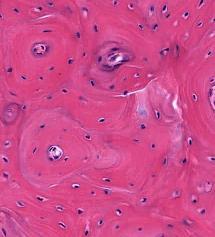

Osteosarcoma is the most common primary, malignant tumor of bone. The cancerous cells derive and from mesenchymal cells and are noted for their production of bone matrix. Osteosarcomas are associated with mutations in the retinoblastoma gene (RB) and p53. In the image, note the extensive, lace-like bone laid down by the cancerous cells. The cancerous cells vary in size and often contain very large nuclei.